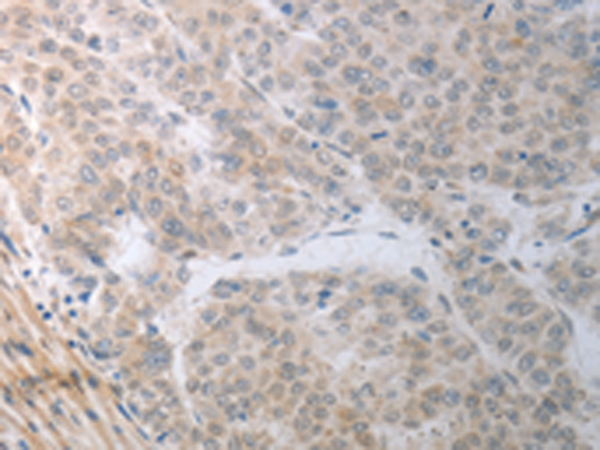

分类: 科研抗体货号: P11097别名: PRMT4应用: IHC反应种属: Human, Mouse, Rat